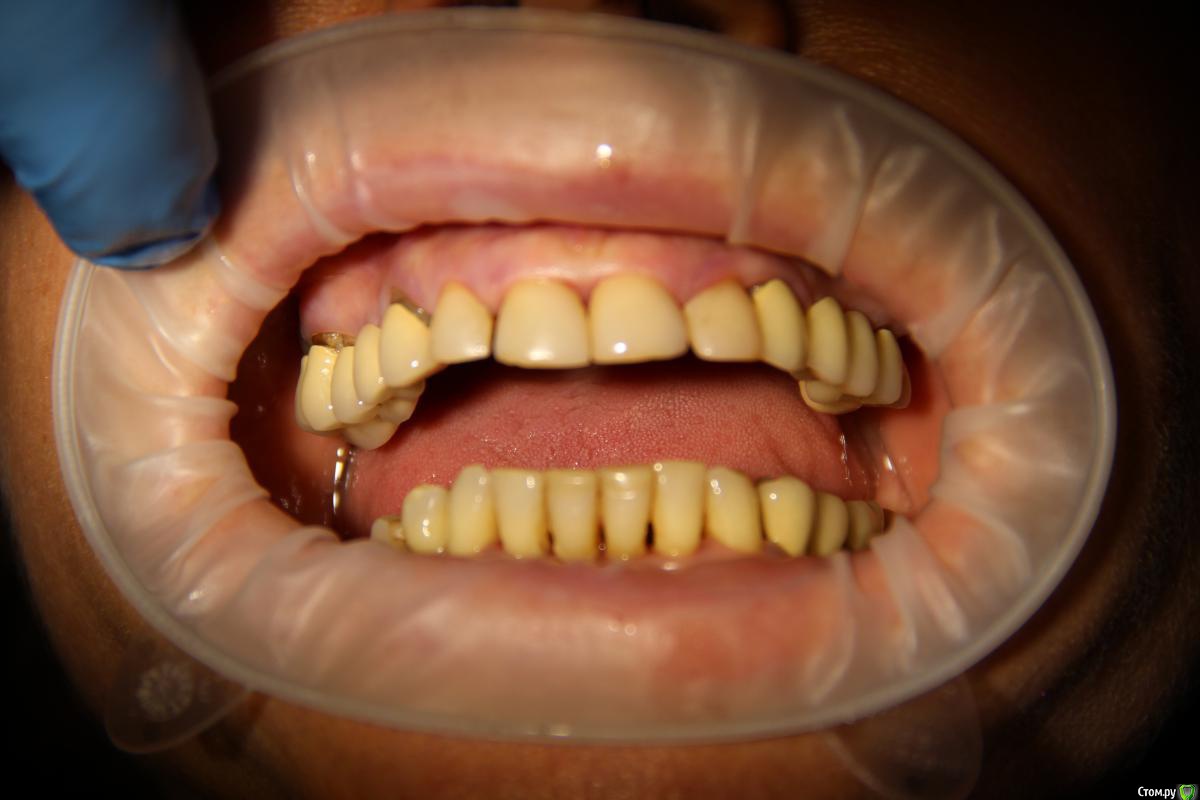

Популярный пост Abuk Опубликовано 24 ноября, 2015 Популярный пост Поделиться Опубликовано 24 ноября, 2015 Планировали 8 имплантатов.Буду рад конструктивной критике.Фото с мокап.Через 6 днейДалее хотели поставить 6 ки, она отказалась (не хотели синусы)и решили все по-другому .Через 2мес пришла с отколотыми консолями )Прошу прощения ,что ортопедию выложил не в том разделе), не хотел делить. 26 1 Ссылка на комментарий

Abuk Опубликовано 24 ноября, 2015 Автор Поделиться Опубликовано 24 ноября, 2015 (изменено) Радикально Вы. Что оставили ей после имплантации-это инд аббатменты? На них мокап одели и нагрузили сразу? У всех был торк хороший? Или это временные абб? Что за систему использовали? В планах консоль назад, правильно я понимаю?Спасибо.увидев такую работу,сам так же подумал бы). Но там подвижность 2-3 ст. ближе к 3. Мосты болтались ,2 ки в хлам. 1 ки только стабильны. Снимал мосты,проводил кюретаж. Решил дернуть.Абатманы временные, тех. сделал на них коронки. Система анкилоз. Работа,на посл. фото, постоянная . Имплы в области 4 и по одному моляру ,консоли. Мок ап был до имплантации . По нему шаблон. Стабильность 15 -20 на 23 , остальное больше 30. Изменено 24 ноября, 2015 пользователем Abuk 1 Ссылка на комментарий